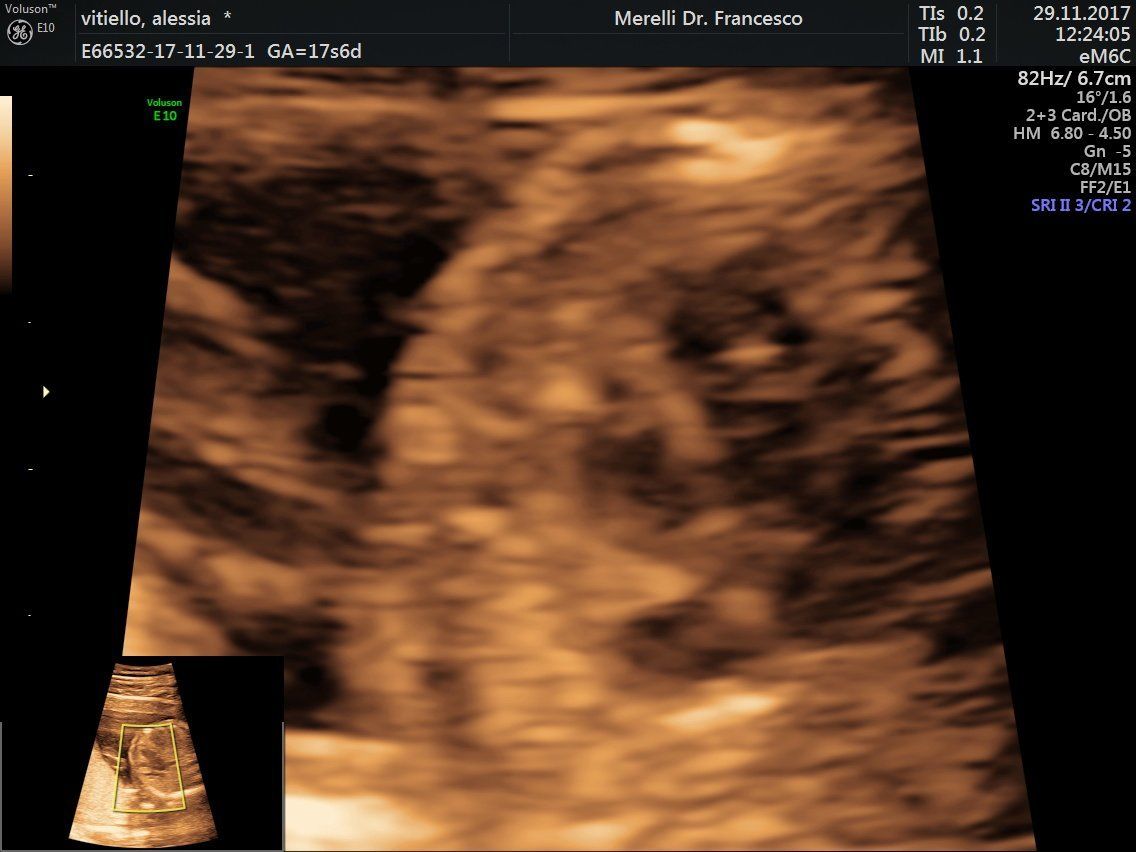

Il dr. Merelli esegue anche l'

ecografia ostetrica ginecologica tridimensionale.

- ecografie ostetrico - ginecologiche

- ecografia 4d